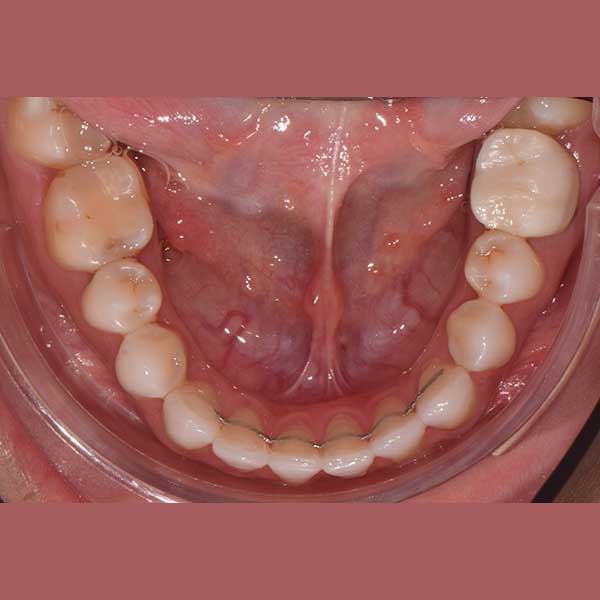

BEFORE

This patient has suffered from spaces between her lower teeth due to an unknown reason, and by examining the teeth, I found that the gums were healthy and fixed braces were installed and the spaces were closed successfully in addition to the paving of the upper teeth successfully as well.